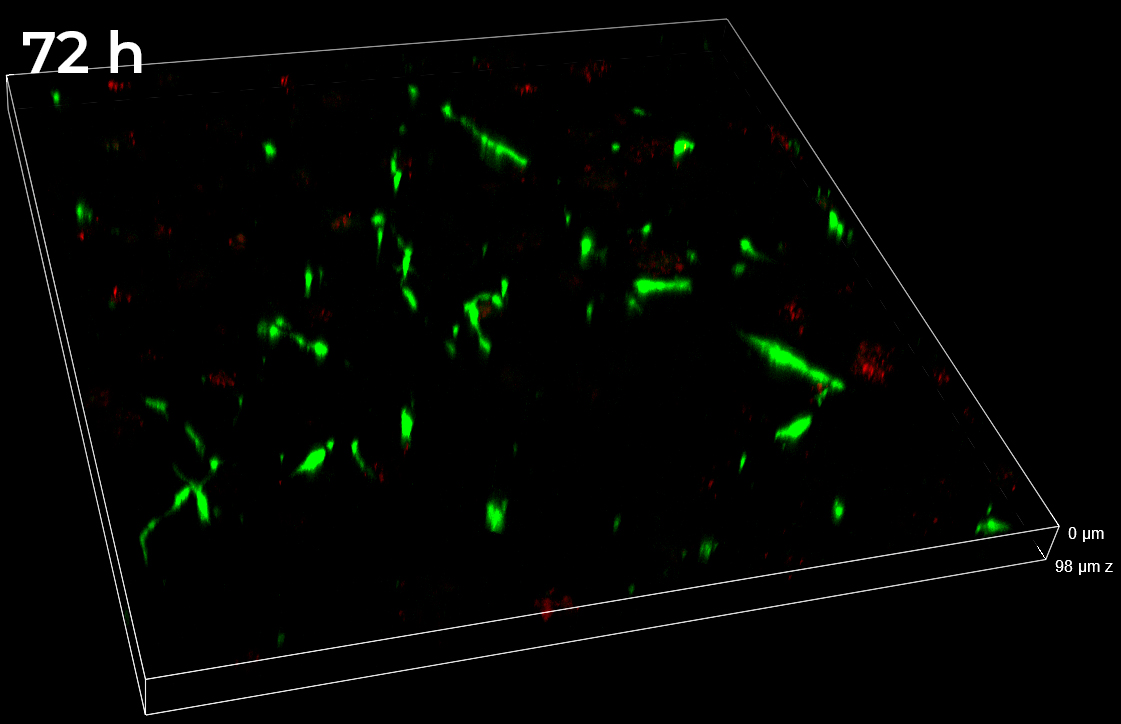

Data obtained from live monitoring of co-cultures in VITVO were compared with end-point readouts from fixed samples at specific time points post-treatment (24 and 72 h, Figure 8). 3D comparison among three different FOVs confirmed a homogeneous distribution of cells without any significant inter-field difference. These data point out that AD-MSCs TRAIL were persisted over time, instead of A673 tumor cells which massively decreased in their signal and cell density (Figure 8).

Figure 8. Z-stacks on VITVO FOVs collected and fixed at different time points with spinning disk. 3 different FOVs corresponding to 24 h and 72 h post-treatment fixed sample, respectively (10x objective magnification).